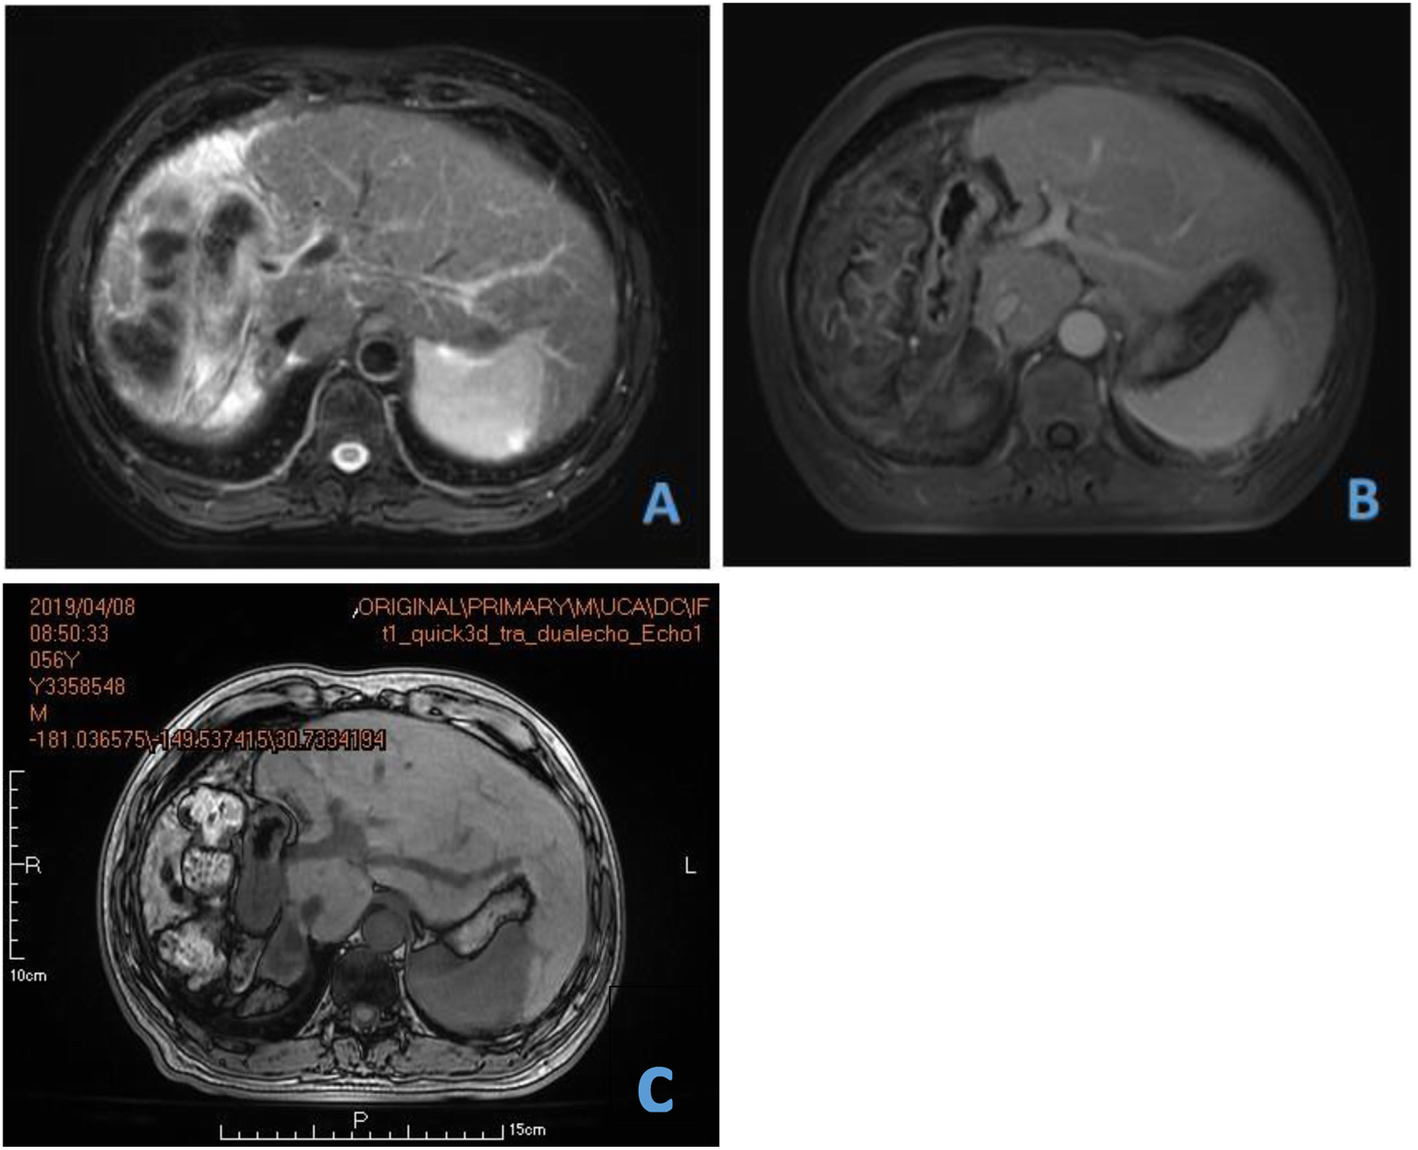

Fig. 6From: First two-stage robotic ALPPS in HCC patients with hepatic vein invasion: a step-by-step procedure from a clinical caseOne month (a), 5 months (b) and 11 months (c) MRI after the operationBack to article page